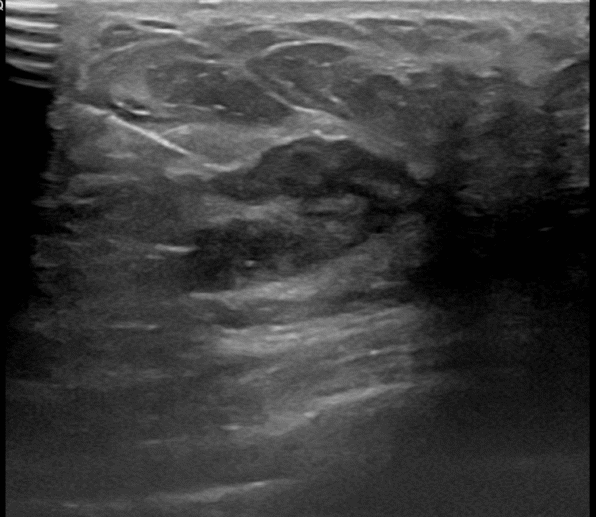

상기환자는 만져지는 멍울로  내원하신 50대후반

여성분으로 의심스러운 좌측혹 조직검사 시행해 침윤성암으로 진단되었습니다